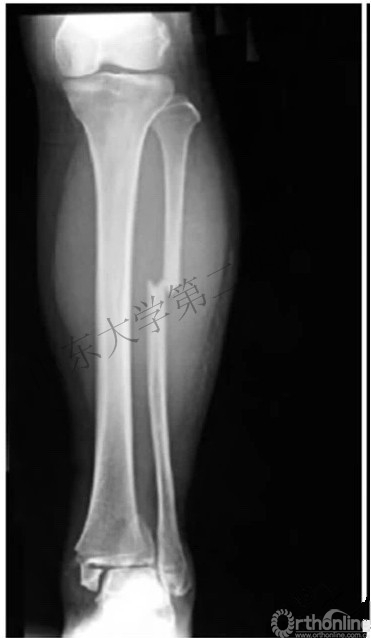

瑞麟导读:Maisonneuve骨折是踝关节骨折中一种特殊的类型,分型中属于LH旋前外旋III度及旋前外旋IV度、Weber分型中的C型骨折。

因其存在腓骨高位的骨折,比较容易漏诊,在查看患者时要特别注意小腿近端的疼痛及压痛,X片检查时尽量拍摄胫腓骨全长片。

Maisonneuve骨折(MFF)是一种特殊类型的踝关节骨折,指由外旋暴力导致的腓骨近端骨折,常合并多种结构损伤。由法国医生Maisonneuve(Dupuytren的学生)于1840年首先报道。

1. 骨间膜损伤及腓骨高位骨折

五、Maisonneuve骨折的诊断

2. 对于踝关节损伤的患者应注意对腓骨近端的查体,并行胫腓骨全长X线片。